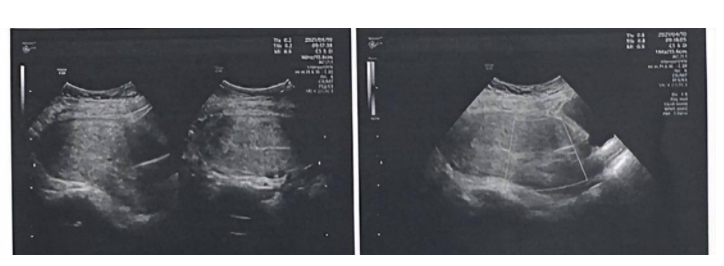

患者入院后完善相关检查,晚期胎儿超声检查结果显示羊水指数8.4cm,胎心率145bpm,脐带结构正常,临床孕周:37w,超声孕周38w,单活胎头位。

于是入院第二天,患者在全麻下行子*下段剖宫术,以LOA位助娩一位活男婴,出生后Apgar评分8-9-10-10,术中见脐带绕颈2周,体重3620g,身长50厘米,胎盘人工娩出,薄膜完整。产时危险300ml,手术进过顺利。术前术后给予抗生素预防性抗消息,缩宫素促进子*收缩。

脐带绕颈是B超检查上的一种专业术语,是指脐带围绕胎儿脖子1圈或多圈,B超检查通过检查胎儿脖子上有无压痕来推测有无脐带绕颈。